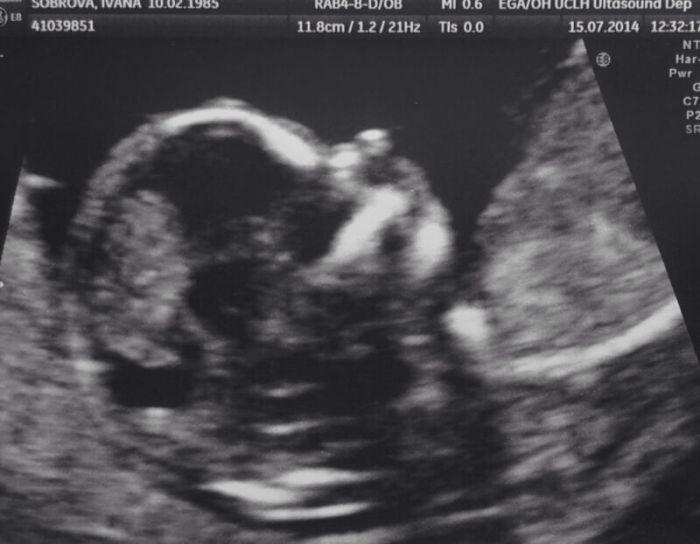

Ahoj holky, - ten prispevek se mi odeslal nechtene a nevim, jak to smazat - pisu z mobilu. Nektere si me mozna pamatujete, kdysi jsem sem psala, ale pro nedostatek casu jsem prestala, mam dve prace totiz :// Mimco cekam podle menses 23.1. a podle ultrazvuku z 21.1. :) = za chvilku!!! Pohlavi neznam, je to moje prvni dite a prejeme si chlapecka :)) To jen tak na uvod.. A ted to "hlavni" prosim vas.. Jdete se nekdo ockovat proti chripce a jeste necemu (coz nevim, jak prelozit do cestiny) - me bylo nabidnuto resp. dost me k tomu v nemocnici vedou, at se necham ja I partner ockovat. Ja mam navic krevni skupinu negativni, takze stejne na nejakou injekci uz jit musim (neco kvuli protilatkam) Nejsem precitlivela nebo tak.. Ale neprijde vam to moc? Chripka potom ten "neco caught" coz fakt netusim co je a potom protilatky.. Diky za pripadne komenty :) PS: Moc vam vsem gratuluji k perfektnim vysledkum a preji jen same dobre zpravy! PS2: Posilam fotku meho miminecka a meho bricha, pro ktere si uz nemohu ani poradne zavazat boty haha Mejte krasny den

dnes nam drobek konecne ukazal sulinka, takze kluk :)